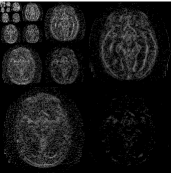

To examine the performance of our approach with brain MRI data when the assumptions of similarity between consecutive scans is not valid, we used retrospectively acquired data of a patient with GBM. The patient was scanned twice within an interval of five months, and exhibited changes between scans that occupy more than 50% of the brain region. We used T2-weighted FSE sequence (matrix: res = , 36 slices with thickness and no gap, TR/TE=, echo-train length=, flip angle=). We registered the follow-up scan to the baseline scan and examined the results of LACS-MRI (), CS-MRI and TCS-MRI with acceleration factors of 4, 6.4, and 10.6.

Table 3 shows the SNR values for different reconstructions and Figure 6 shows reconstruction results visually, at acceleration factor of 4 (25% of the k-space). In this case, there are major changes between the baseline and the follow-up scans due to therapy response. As a result, TCS-MRI exhibits poor performance in the vicinity of the changing tumor, since it is partially based on similarity between the consecutive scans, an assumption which is not valid in this case.

LACS-MRI, however, convergences to a result which is similar to CS-MRI. This is obtained thanks to the adaptive sampling and the weighting mechanism embedded in LACS-MRI, which reduces the weight given to the similarity to prior scan in the reconstruction process, if such a similarity does not exist.

Nyquist sampling (baseline)

Nyquist sampling (follow-up)

CS-MRI (follow-up)

TCS-MRI (follow-up)

LACS-MRI (follow-up)

Reconstruction result

Difference image

Reconstruction (zoom)